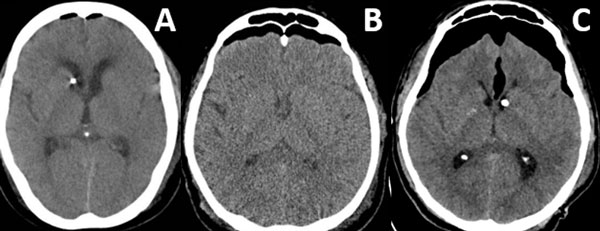

Patrones y grados de NE: NE subdural (Figura 1), se clasificó en 3 grados: leve (menor al espesor óseo), moderado (entre una vez y dos veces el espesor óseo) y severo (dos o más veces el espesor óseo). NE subaracnoideo (Figura 2), se clasificó en 3 grados: leve (confinado a cisternas basales), moderado (cisternas supratentoriales predominio unilateral), severo (generalizado). NE ventricular (Figura 3), se clasificó en: leve (en IV y/o III ventrículo), moderado (alcanzó VL), severo (alcanzó y dilató los VL).

Figura 3. Neumoencéfalo ventricular. A) Leve. B) Moderado. C) Severo.